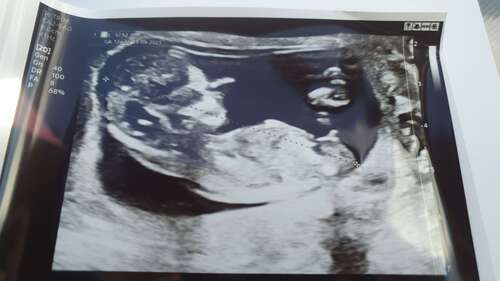

Net weer een echo gehad, 12+2 . Enorm benieuwd! Volgende week geslachts echo

Obv de NUB op je huidige echo zou ik zeggen een jongetje. Ben benieuwd of dat klopt…

Ik zou ook zeggen een jongetje op dit moment